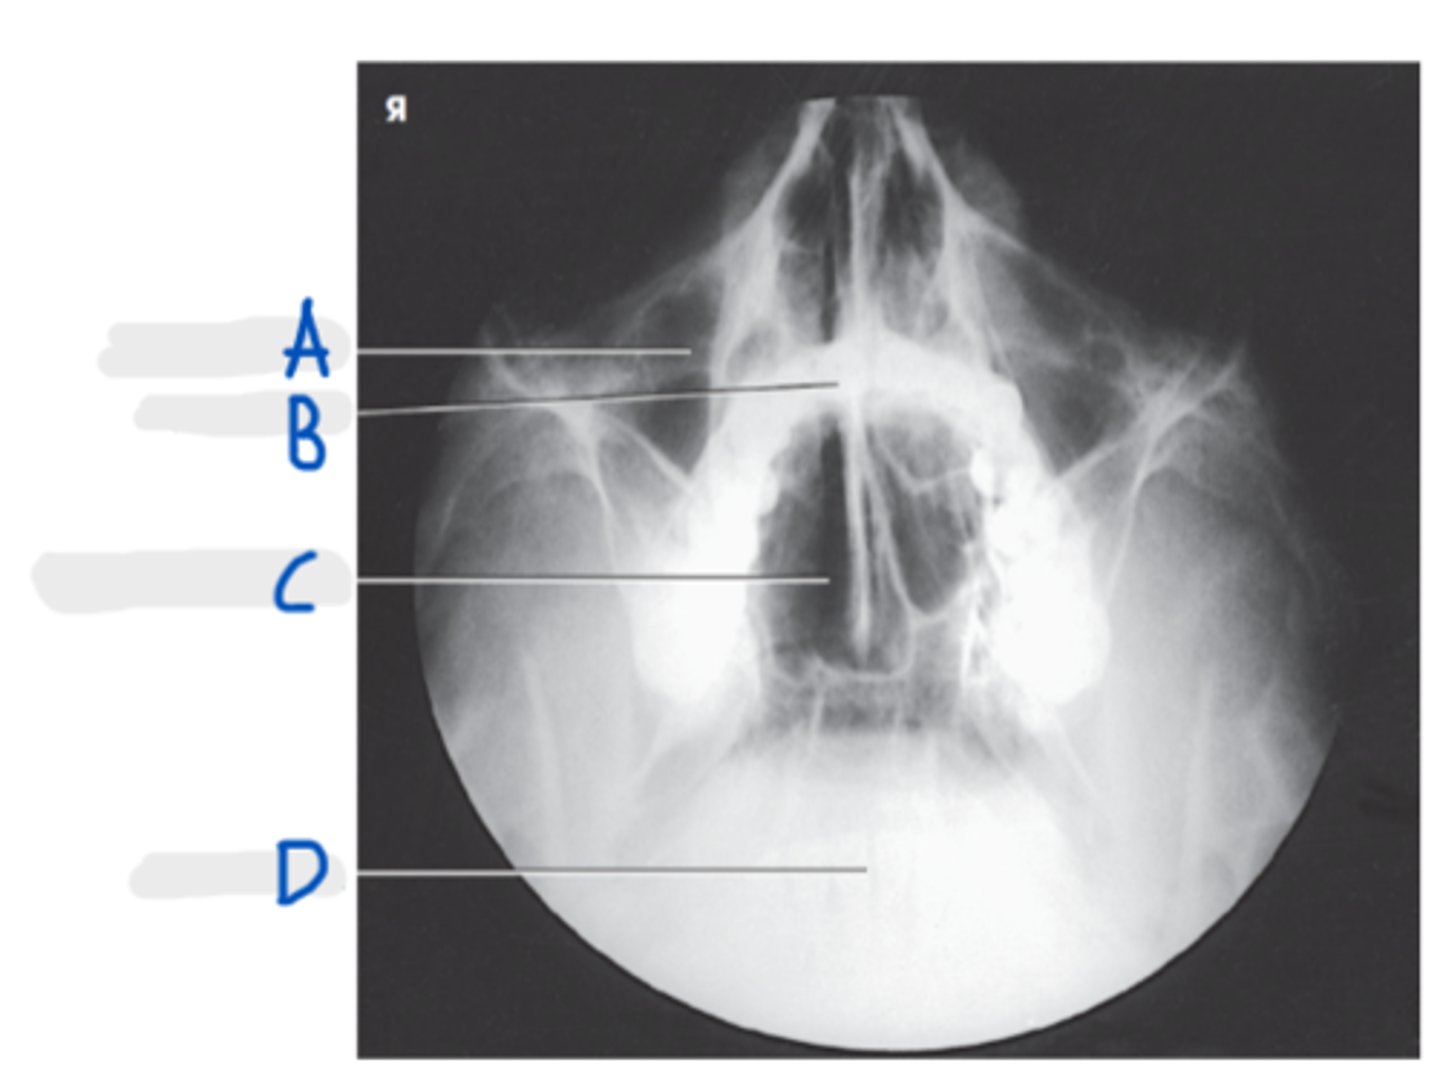

Maxillary sinus

A

Upper teeth

B

Sphenoid sinuses

C

Lower teeth

D

Parietoacanthial Transoral (Open-Mouth Waters)

What projection is this?

Lips-meatal line (LML)

What line is perpendicular to the IR for PA Transoral (Open-Mouth Waters)?

CR exit at acanthion

What is the CR for a PA Transoral (Open-Mouth Waters)?